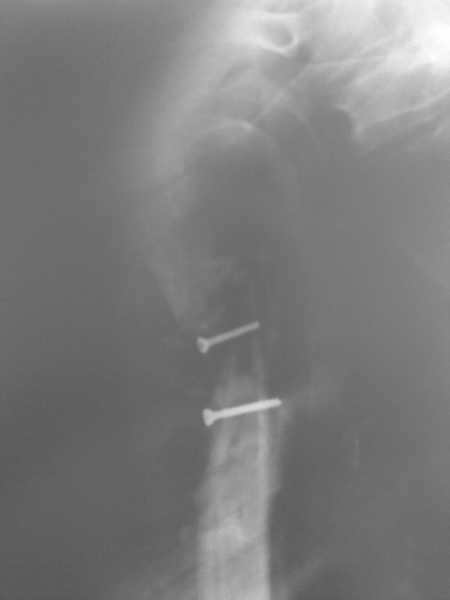

Более года назад пациент был оперирован в одном из НИИТО. При контрольном осмотре через год: болевой синдром, контрактура в локтевом суставе, патолгическая подвижность нижней трети плеча

Неудачный остеосинтез пластиной: поломка винтов, миграция фиксатора. После удаления пластины сформировался гипопластический ложный сустав нижней трети бедренной кости, укорочение н/к 5 см. Выполнялся дистакционный остеосинтез аппратом Илизарова на штифте. Зона ложного сустава "не открывалась". Через 10 месяцев, когда даже регенерат полностью перестроился, консолидации в зоне ложного сустава не наступило, несмотря на стабильную фиксацию и постоянную компрессию(штифт+аппрата на 4 кольцах).